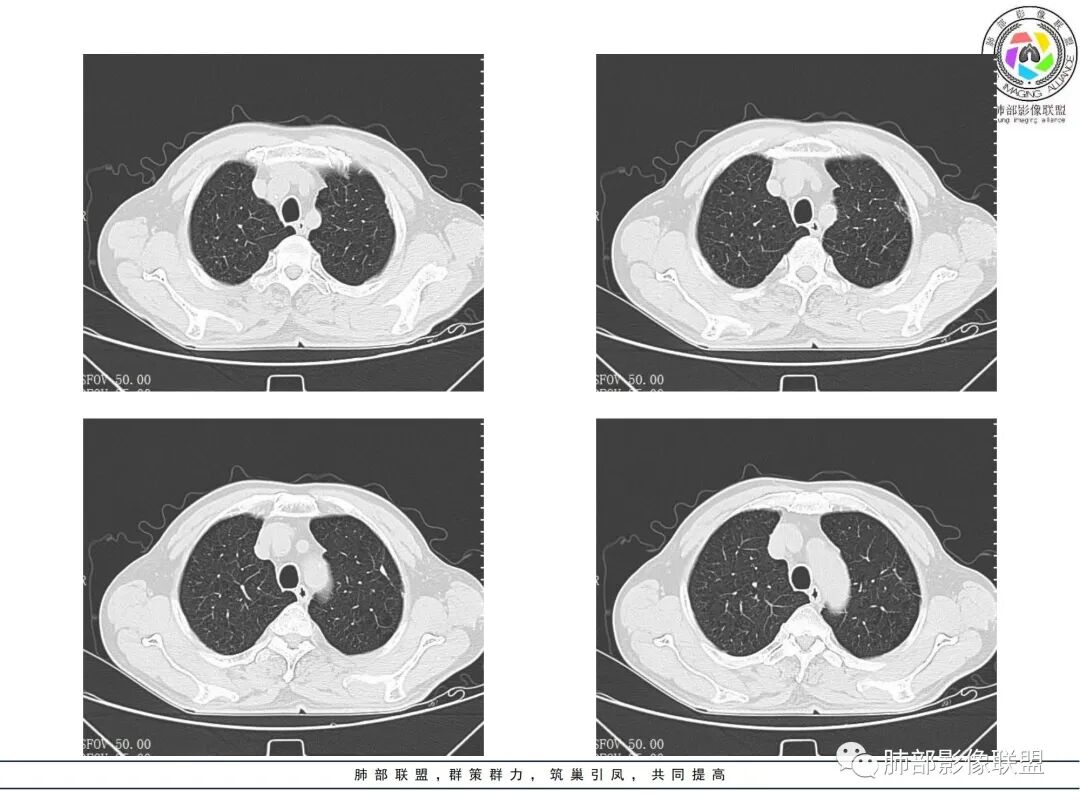

老年男性,肺气肿背景,右肺较大分叶状肿块,密度不均,内坏死空洞形成,坏死区边界不规则,周围多发斑片蜂窝状、网格状高密度影,考虑鳞癌合并感染

老年男性,有咳嗽发热。右肺中上叶团状软组织肿块,周围磨玻璃渗出改变,病灶内密度不均,可见低密度坏死及空洞影,空洞内壁凹凸不平,近肺门侧可见明显大面积坏死。近端支气管堵塞不明显。考虑恶性肿瘤伴感染,腺癌?鉴别鳞癌,感染性病变。

右肺上叶团片状阴影,内见空洞,空洞内壁不光滑,偏心,,增强不均匀强化,内有边界不清晰的坏死,病灶周围可见片状模糊阴影,右下肺也有磨玻璃病灶,Crp高,腺癌

右肺上叶实变,密度不均,内可见小气液平,周磨玻璃影,斜裂稍内凹,右下肺可见斑片影,强化可见血管走行自如,右侧胸腔少量积液,考虑感染性病变,努卡?放线菌?

老年男性,肺气肿背景,右肺上叶及中叶大范围实变影,边界不清,支气管通畅,其内见边缘膨隆软组织块影伴不规则坏死、空洞,增强扫描不均匀强化,洞壁显示不清,血管稍变细,实变影内另见多发囊样影,右肺下叶小片状影,病灶跨叶,炎性指标增高,感染应该有的,不除外合并恶性肿瘤(鳞癌?腺癌?)

男,70,反复乏力、纳差20天,发热1天。胸部CT:肺气肿背景,右肺上叶中叶大团片影,实变十磨玻璃渗出。增强实性斑片影内密度不均,可见多发低密度坏死及不规则空洞影,空洞内壁尚光滑,血管边缘模糊。支气管管壁增厚,管腔通畅。右下叶可见小片渗出影。考虑支气管肺炎进展?病原考虑能形成肉芽肿、坏死空洞的微生物,TB?奴卡?鉴别鳞癌。

老年男性,乏力纳差,进食量明显下降,发热,后期少许黄脓痰,无咯血。无胸痛。未提口腔卫生情况,发热时间段不明确,肺气肿背景,气管内痰拴还是其他?觉得是外朝内进展病灶,右肺多叶段病灶,支气管通畅,支气管壁弥漫增厚,实变病灶内有坏死,坏死边界比较清晰,血管破坏不明显,周围散在磨玻璃,边界模糊,无树芽,实变内可疑小钙化,右侧胸水,肺门纵隔淋巴结无明显肿大。病史不太支持化脓菌感染,真菌里隐球强化不太支持,结核需要排除,厌氧菌感染带排,冠状位矢状位病灶觉得类圆形,临床肿瘤也是不能轻易排除的

发热,炎性指标高。右肺上叶实变影,凝固型坏死,裂隙状空洞,有钙化,有间质结节,考虑感染性病变,TB可能,鉴别肺炎性肺癌。

周围GGO,不能考虑癌性淋巴管炎